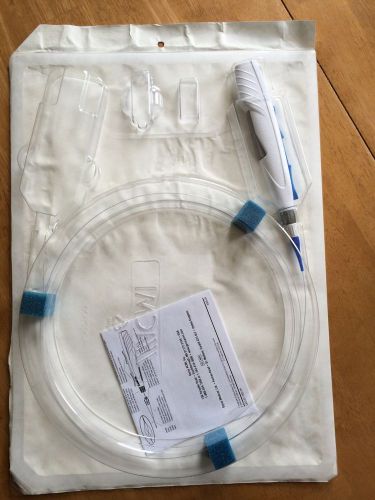

V.A.C. GranuFoam Dressing Medium SensaT.R.A.C. Technology - pckg of 4

VAC SIMPLACE DRESSING SIZE S W/GRANUFORM SPIRAL DRESSING./CANNISTER NEW